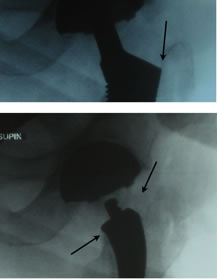

As you can see from this 15 month post-op (now 26 months post-op) there has been visually no changes to x-ray appearance.

Good medial conical flair contact, no distal pedestal, no reactive lines and no apparent medial calcar bone loss.

Note: The lateral cortical neck is retained with the curvature of the stem. This functions like a tension band maintaining strong resistance to both axial and torsional loads. It further provides a physical barrier restricting any potential particulate debris from migrating down the lateral side of the stem.

This curve design also reduces soft tissue injury to the abductors during preparation and stem insertion. |

|

As seen here in these two proximal x-ray comparisons the bottom is a view of the curved neck sparing design size 2 rasp with good proximal fit and excellent maintenance of both the medial and lateral portions of the neck. This was then converted to a short taper style stem and required more removal of both vertical and lateral neck, resulting in a lager stem (size 5) being needed for good implant/bone stability.

This case confirms previous case studies that on average a size two curved neck sparing stem results in a size 5-6 short tapered style stem requiring more vertical medial and lateral neck removal.

It also re-confirms that no special tables or instruments are needed to insert a small curved neck sparing stem in a single incision anterior approach. |